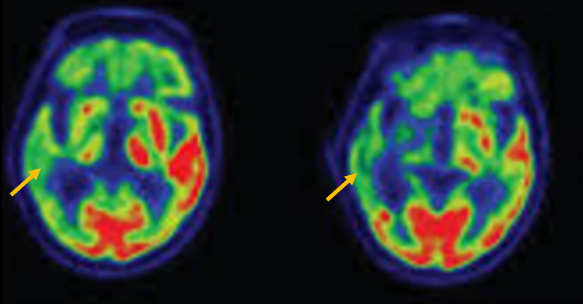

피질 기저핵 변성은 비대칭 증상을 두드러지게 보인다는 점에서 파킨슨병과 비슷합니다. 그러나 파킨슨병과 비교해 보았을 때 양측의 차이가 아주 심하게 나타난다는 특징이 있습니다. 질병 초기에 한쪽 손으로 동작을 하거나 계획된 행동을 하는 기능이 현저하게 떨어집니다. 간단한 손가락 모양도 따라 하지 못하는 현상을 보입니다. 또한 의지와 상관없이 제멋대로 움직이는 통제불능 손이 나타날 수 있습니다. 체위 떨림, 경축, 운동 완만과 같은 파킨슨병에서 볼 수 있는 증상들은 피질 기저핵 변성에서도 관찰될 수 있습니다. 또한 집중력 장애, 수행 장애, 이름 대기나 언어의 유창성이 떨어지는 등 전두엽 및 두정엽과 관련된 인지 장애가 나타납니다. 피질 기저핵 변성은 뇌 자기공명영상(MRI)에서 증상의 반대쪽 전두두정엽의 위축 소견이 특징적으로 나타납니다. 뇌포도당 양전자 단층촬영(PET)에서도 전두엽, 뇌기저핵에 비대칭적인 대사 저하의 소견이 보입니다.

[피질기저핵 변성 환자의 뇌자기공명영상에서 확인되는 비대칭 뇌피질의 소견]

[피질기저핵 변성 환자의 뇌포도당 양전자 단층촬영에서 확인되는 비대칭적인 대사 기능 저하]4. 루이소체 치매(Dementia with Lewy bodies)